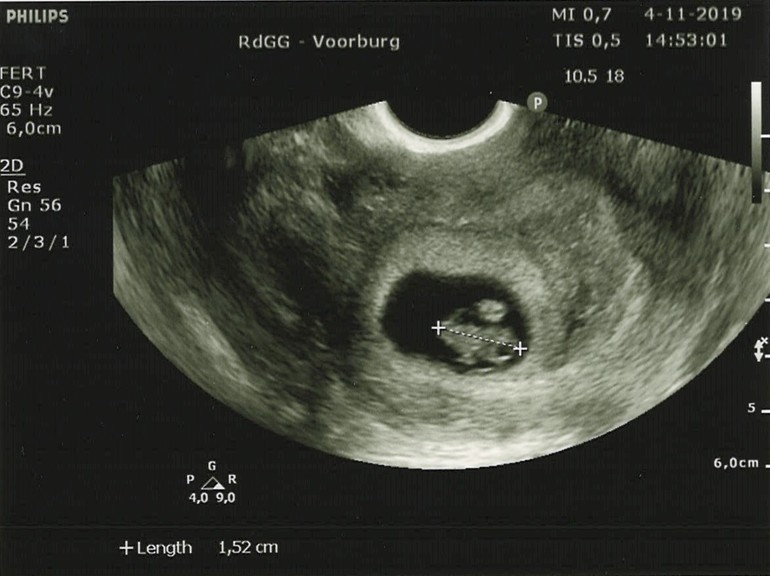

Второе УЗИ 7+4 недель (35 ДПП)

Мой медвежонок вырос в 2 раза, и по УЗИ ктр - 1,52см. По всем параметрам беременность благополучная, мой репродуктолог сказала, что вероятность хорошего исхода этой Б 90%.